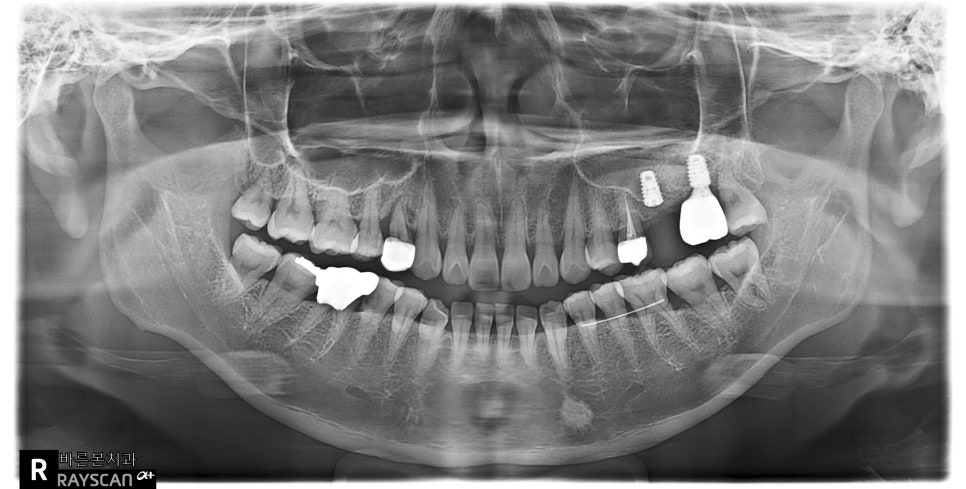

22.11.11(초진) – 43y 백OO님

환자분의 x-ray 사진입니다.

빨강색동그라미 치아인데요,

이미 가장 뒷쪽 어금니 자리에는

임플란트치료가 되어있습니다.